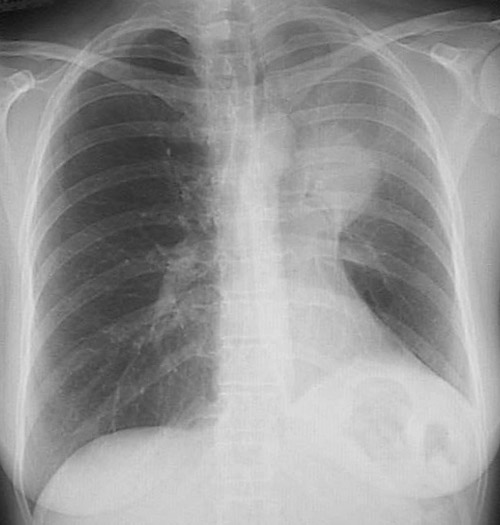

![]() | The chest radiograph shown here demonstrates a carcinoma at the left hilum in the upper lobe that has caused post-obstructive atelectasis (with mediastinal shift to the left) and a lipid pneumonia, marked by haziness and infiltrates distal to the mass. |